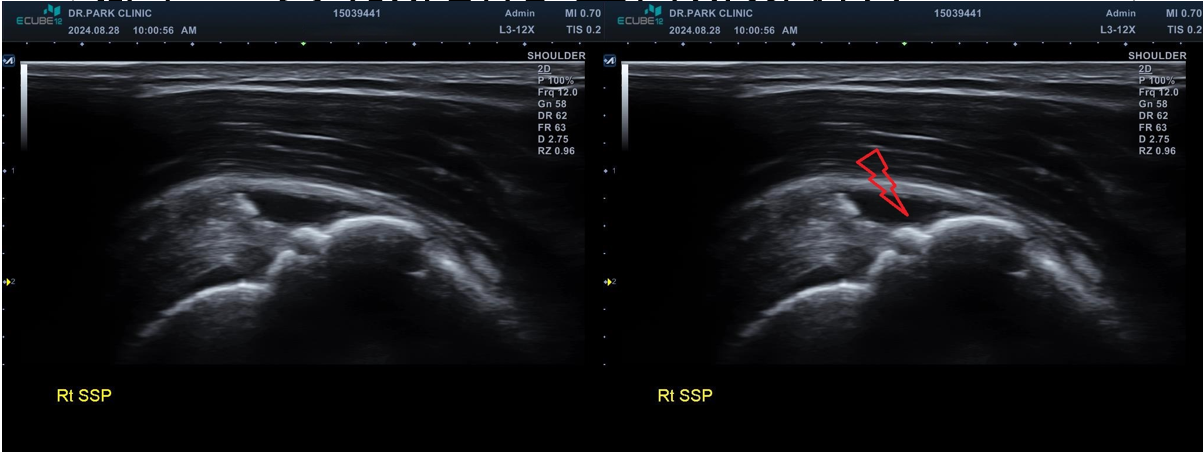

마지막 초음파에서는 어깨 극상근의 파열 소견이 관찰되고 있습니다. 정확한건 mri 를 찍어봐야 하겠지만 찢어진 길이와 정도로 봐서는 수술이 필요한 극상근 전층파열로 생각이 됩니다.

나 : 초음파상에서 어깨 극상근이라는 힘줄 파열이 관찰되네요. 이게 제일 문제입니다

환자 : 많이 심한가요? 수술해야 하나요?

나 : 수술 여부는 MRI를 찍어야만 정확히 결정되는 거지만.... 초음파에서 이정도 파열인 경우 보통 수술 하는게 좋습니다.